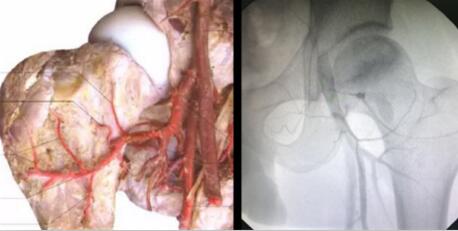

临床证实:股骨头缺血性坏死之所以会坏死,首先是各种原因(激素、酗酒、外伤等)造成血液粘稠、以及形成大量的脂肪颗粒和血栓等,然后随着血液流淌,这些杂质不断沉积最终堵塞了股骨头的供血血管。而股骨头血供跟其他骨头不一样,它只有三根主要的动脉血管供应,如果血管堵塞了,骨细胞没有得到充足的营养供应,就会慢慢“饿”死,最终导致股骨头塌陷、坏死。 因此,只有疏通了这三根血管,同时建立起侧支循环,才能彻底解决了股骨头缺血性坏死的病根难题!如何精准检查堵塞血管并对症融通、恢复股骨头血运成为治疗股骨头坏死的核心关键所在!

广大股骨头坏死患者迫切盼望着能够有一种科学的治疗方案,既能保住股骨头不置换,又能对身体无较大损伤,同时能有效避免再次复发的治疗方案。无疑,从病根出发,以“疏通血堵、恢复血供”为核心的““可视血堵融通术结合血液净化”综合治疗”为股骨头坏死保髋、保头治疗提供了全新的选择。突破了传统药物治疗无效、人工关节置换局限性较大等问题,真正得到了广大股骨头缺血性坏死患者的认可。